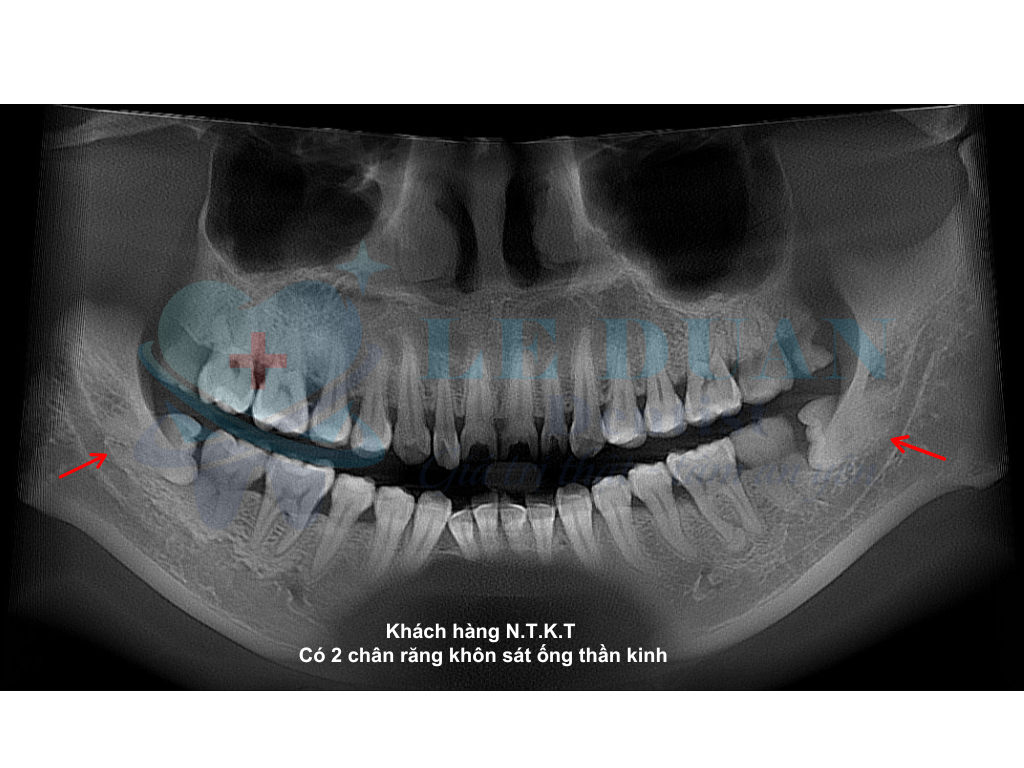

Tổn thương dây thần kinh: Thường gặp ở răng khôn hàm dưới có chân răng sát ống dây thần kinh răng dưới hoặc chui vào trong ống răng dưới.

Dấu hiệu nhận biết:

-

Tê môi, cằm hoặc lưỡi

Cảm giác tê kéo dài

Xử lý: Đa số trường hợp hồi phục sau một thời gian theo dõi và hỗ trợ bằng vitamin nhóm B, laser, hoặc các phương pháp khác.